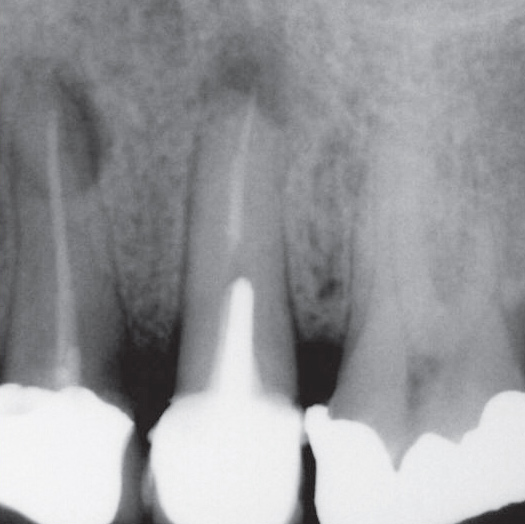

Before

After

Before Root Canal treatment

After Root Canal treatment